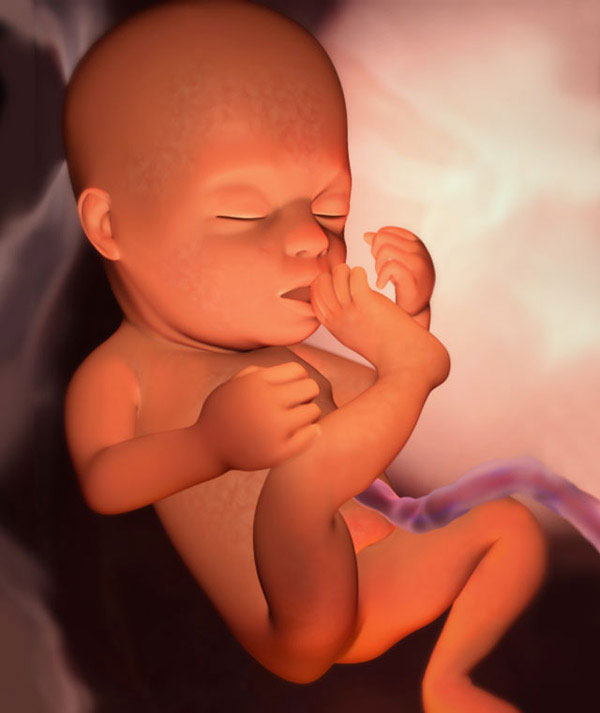

fetus at week 20

Inside you, a real man grows up. It has proportions almost like that of a newborn. Growth is 14-16 cm, and weight is about 260 g. The fetus spends almost all day at rest, and moves only a few hours every day. The tiny brain sends signals, and your baby "tries the forces":

• moves the arms and legs;

• turns with the whole body;

• moves his head;

• opens and closes a mouth;

• sucks fingers (usually "comes across" big);

• sometimes grabs the umbilical cord;

• slightly inflates the chest, as if breathing.